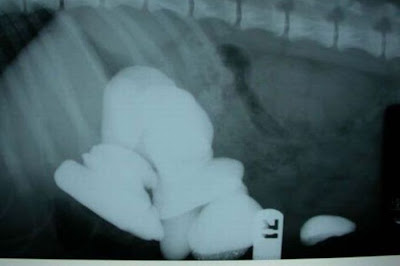

130 Nails